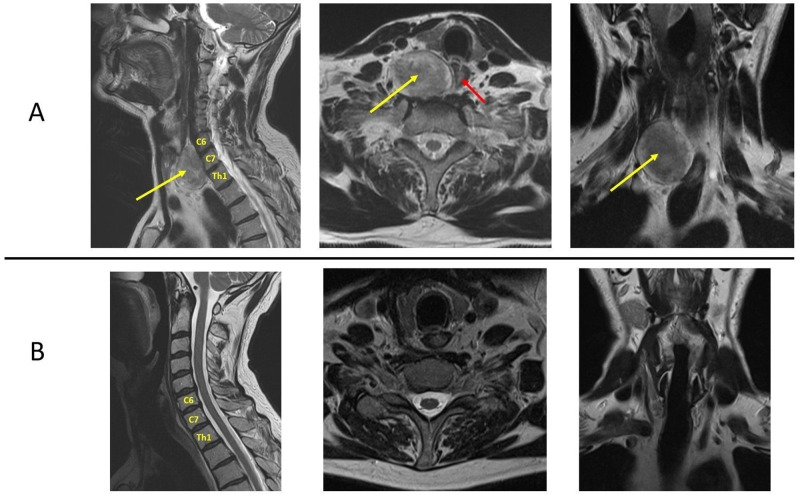

Case report: A 52-year-old male patient sought medical advice on account of intermittent dysphagia and a sense of pressure in the neck, in the absence of pain or neurological deficits. A magnetic resonance (MRI) scan and a subsequent open/surgical biopsy revealed a large schwannoma on the anterior aspect of the spine at C6-C7-Th1 causing compression of the oesophagus. Following a neurosurgical consultation, a radical gross resection of the tumour was carried out from an anterior approach, with no neurological complications. A histological examination of the tumour confirmed the initial diagnosis and a follow-up MRI scan demonstrated complete resection.

Conclusion: This case of successful treatment of a large schwannoma at the C6-C7-Th1 level highlights the importance of both MR imaging and biopsy in pre-operative planning. An anterior approach, routinely employed in cervical spine surgery, made it possible to perform a radical resection without neurological complications or the need to stabilise the cervical spine, which expedited the patient's return to full fitness.